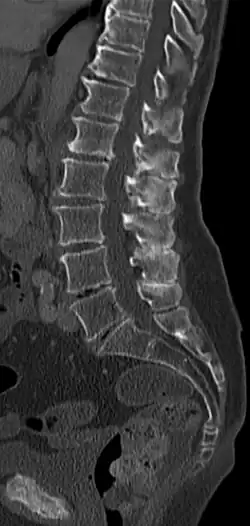

Maladie de Baastrup

La maladie de Baastrup est une pathologie caractérisée par une friction entre les apophyses épineuses des vertèbres lombaires. En réponse au stress subi, le tissu osseux s'élargit à l'extrémité de l'apophyse et accroît en fait la pathologie.